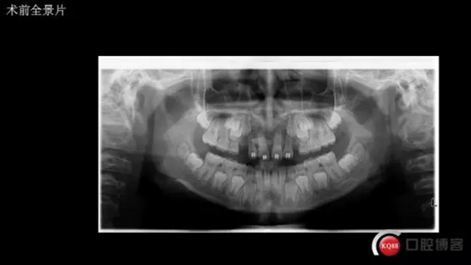

三年半前,家長領著小孩前來要求矯正牙齒,男,約八歲,兩中切牙間隙約12MM,有一多生牙,全景片顯示深處還橫著一顆,也許正處叛逆期,小孩非常的調皮,經(jīng)過幾次的各種哄和商談,也可能為了好看,終于勉強同意先拔掉露出的多生牙,前牙片斷弓關閉間隙